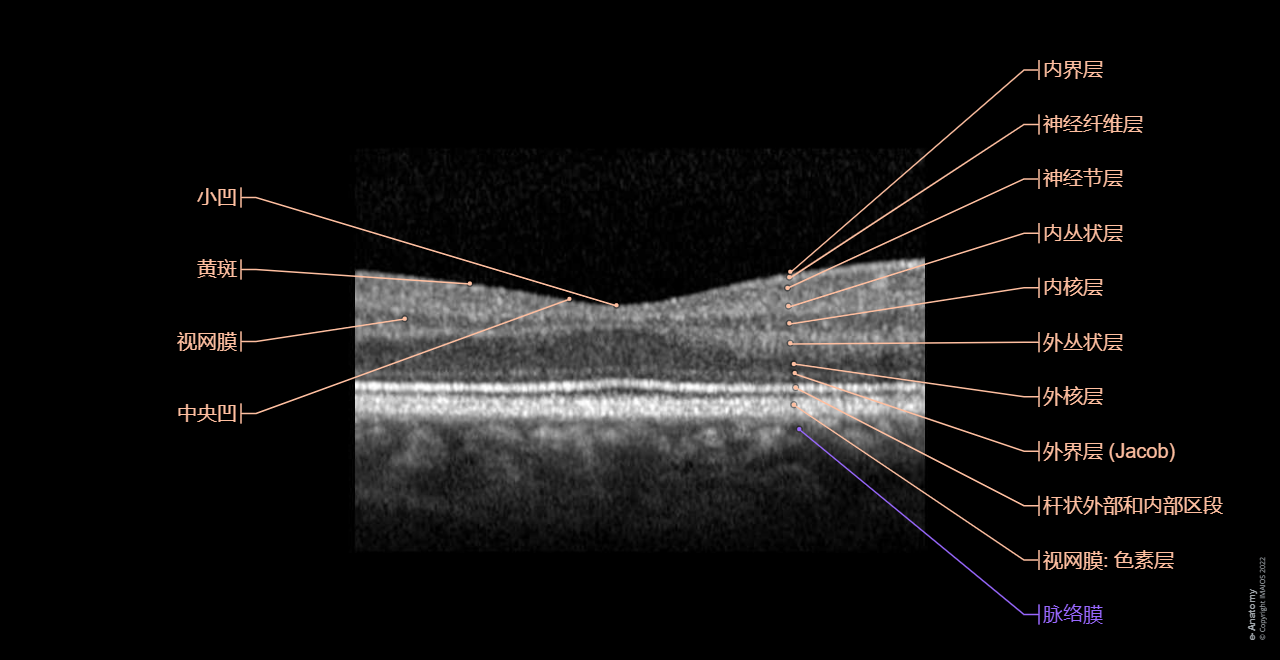

光学相干断层扫描 (OCT)